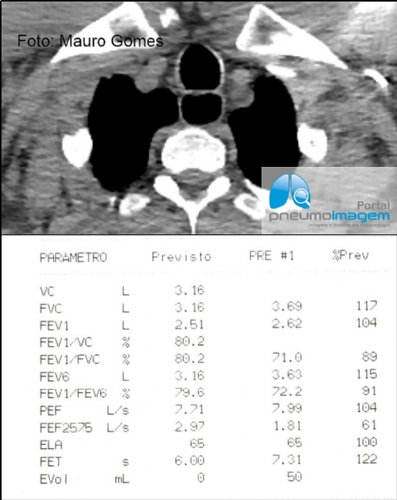

CASO CLÍNICO #61Homem, 69 anos, possui asma alérgica e eosinofílica há 20 anos e vem bem controlado apenas com o uso de corticoide inalatório (mometasona). Há cinco anos apresenta mal-estar noturno e um episódio referido de pneumonia, quando foi suspeitada e confirmada Doença do Refluxo Gastroesofágico. Mesmo sob tratamento, passou a apresentar leve cornagem ao exame clínico. Histórico de arritmia cardíaca e necessidade de implante de marca-passo.

Como você interpreta a espirometria? Que exames você solicitaria para fazer o diagnóstico? Deixe seus comentários abaixo.

A 69-year-old man has had allergic and eosinophilic asthma for 20 years and has been well controlled only with the use of inhaled corticosteroids (mometasone). He has had nocturnal malaise for five years and a reported episode of pneumonia, when Gastroesophageal Reflux Disease was suspected and confirmed. Even under treatment, he started to show discreet pitched squeal coming from lungs when inhaling by auscultation. History of cardiac arrhythmia and need for pacemaker implantation.

How do you interpret the spirometric test? What tests would you order to make the diagnosis? Write your comments below.